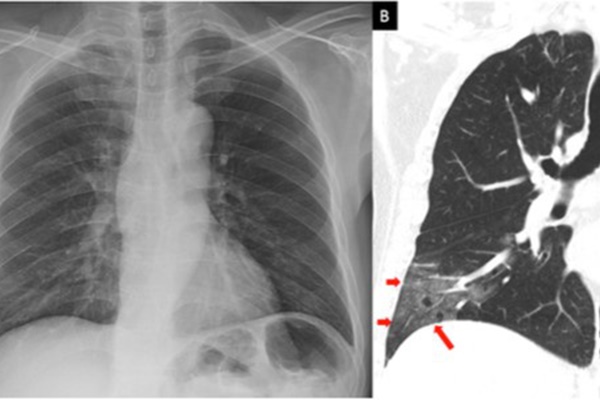

Theo thông tin từ Bệnh viện Bệnh Nhiết đới, TP.HCM trường hợp bệnh nhân nặng số 91 (phi công, quốc tịch Anh) đang điều trị tại bệnh viện: Hiện tại tình trạng bệnh nhân ổn định, không sốt, mạch huyết áp bình thường, chức năng phổi có cải thiện khá hơn sau tập vật lý trị liệu hô hấp.